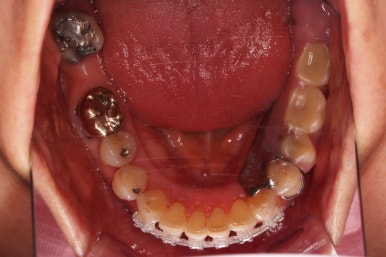

초진 시 입안의 모습입니다.

일반적인 교정을 하기에는 적합한 모습은 아니었어요.

치아는 군데군데 없고 임플란트도 있고 브릿지로 연결된 치아도 있으며 전반적인 잇몸 상태도 좋지 못했어요.

앞니가 벌어져 있고 뻗쳐 있으며 잇몸에서 쏙 빠져나와 있는 듯한 느낌이었어요.